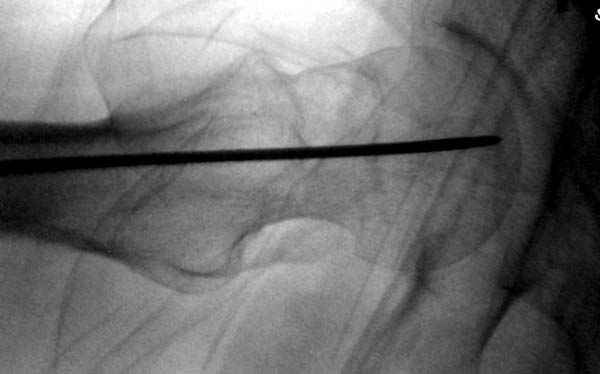

На второй день после выписки упал дома. Снимки приложены. Коллеги рекомендуют удаление шурупа и вытяжение. Что делать?

Привет из солнечного Будапешта с Eurotrauma-2008. Да, замечательный пример. Получается, профилактику расхождения отломков шейки надо было проводить каким-то реконструкционным или проксимальным гвоздем, причем сразу длинной версией. Сейчас, наверно, так и надо бы сделать.

Правильно, ситуация изменилась, как говорят у нас теперь "different animal", надо решать проблему подвертельного перелома. При наличии различных вариантов фиксаторов, включая Страйкер Гамма 3, мы выбрали DePuy Antegrade Trachanteric Nail из-за многовариантности проксимальной фиксации и двойного изгиба. Вводится через вертел под 8 градусным углом, и есть достаточный передний диафизарный изгиб, предупреждающий пенетрацию дистального переднего кортекса.

Но ведь и головка бедра сползла в варус - отчего ограничились только фиксацией подвертельного перелома, а не убрали винты и не сделали репозицию шейки?